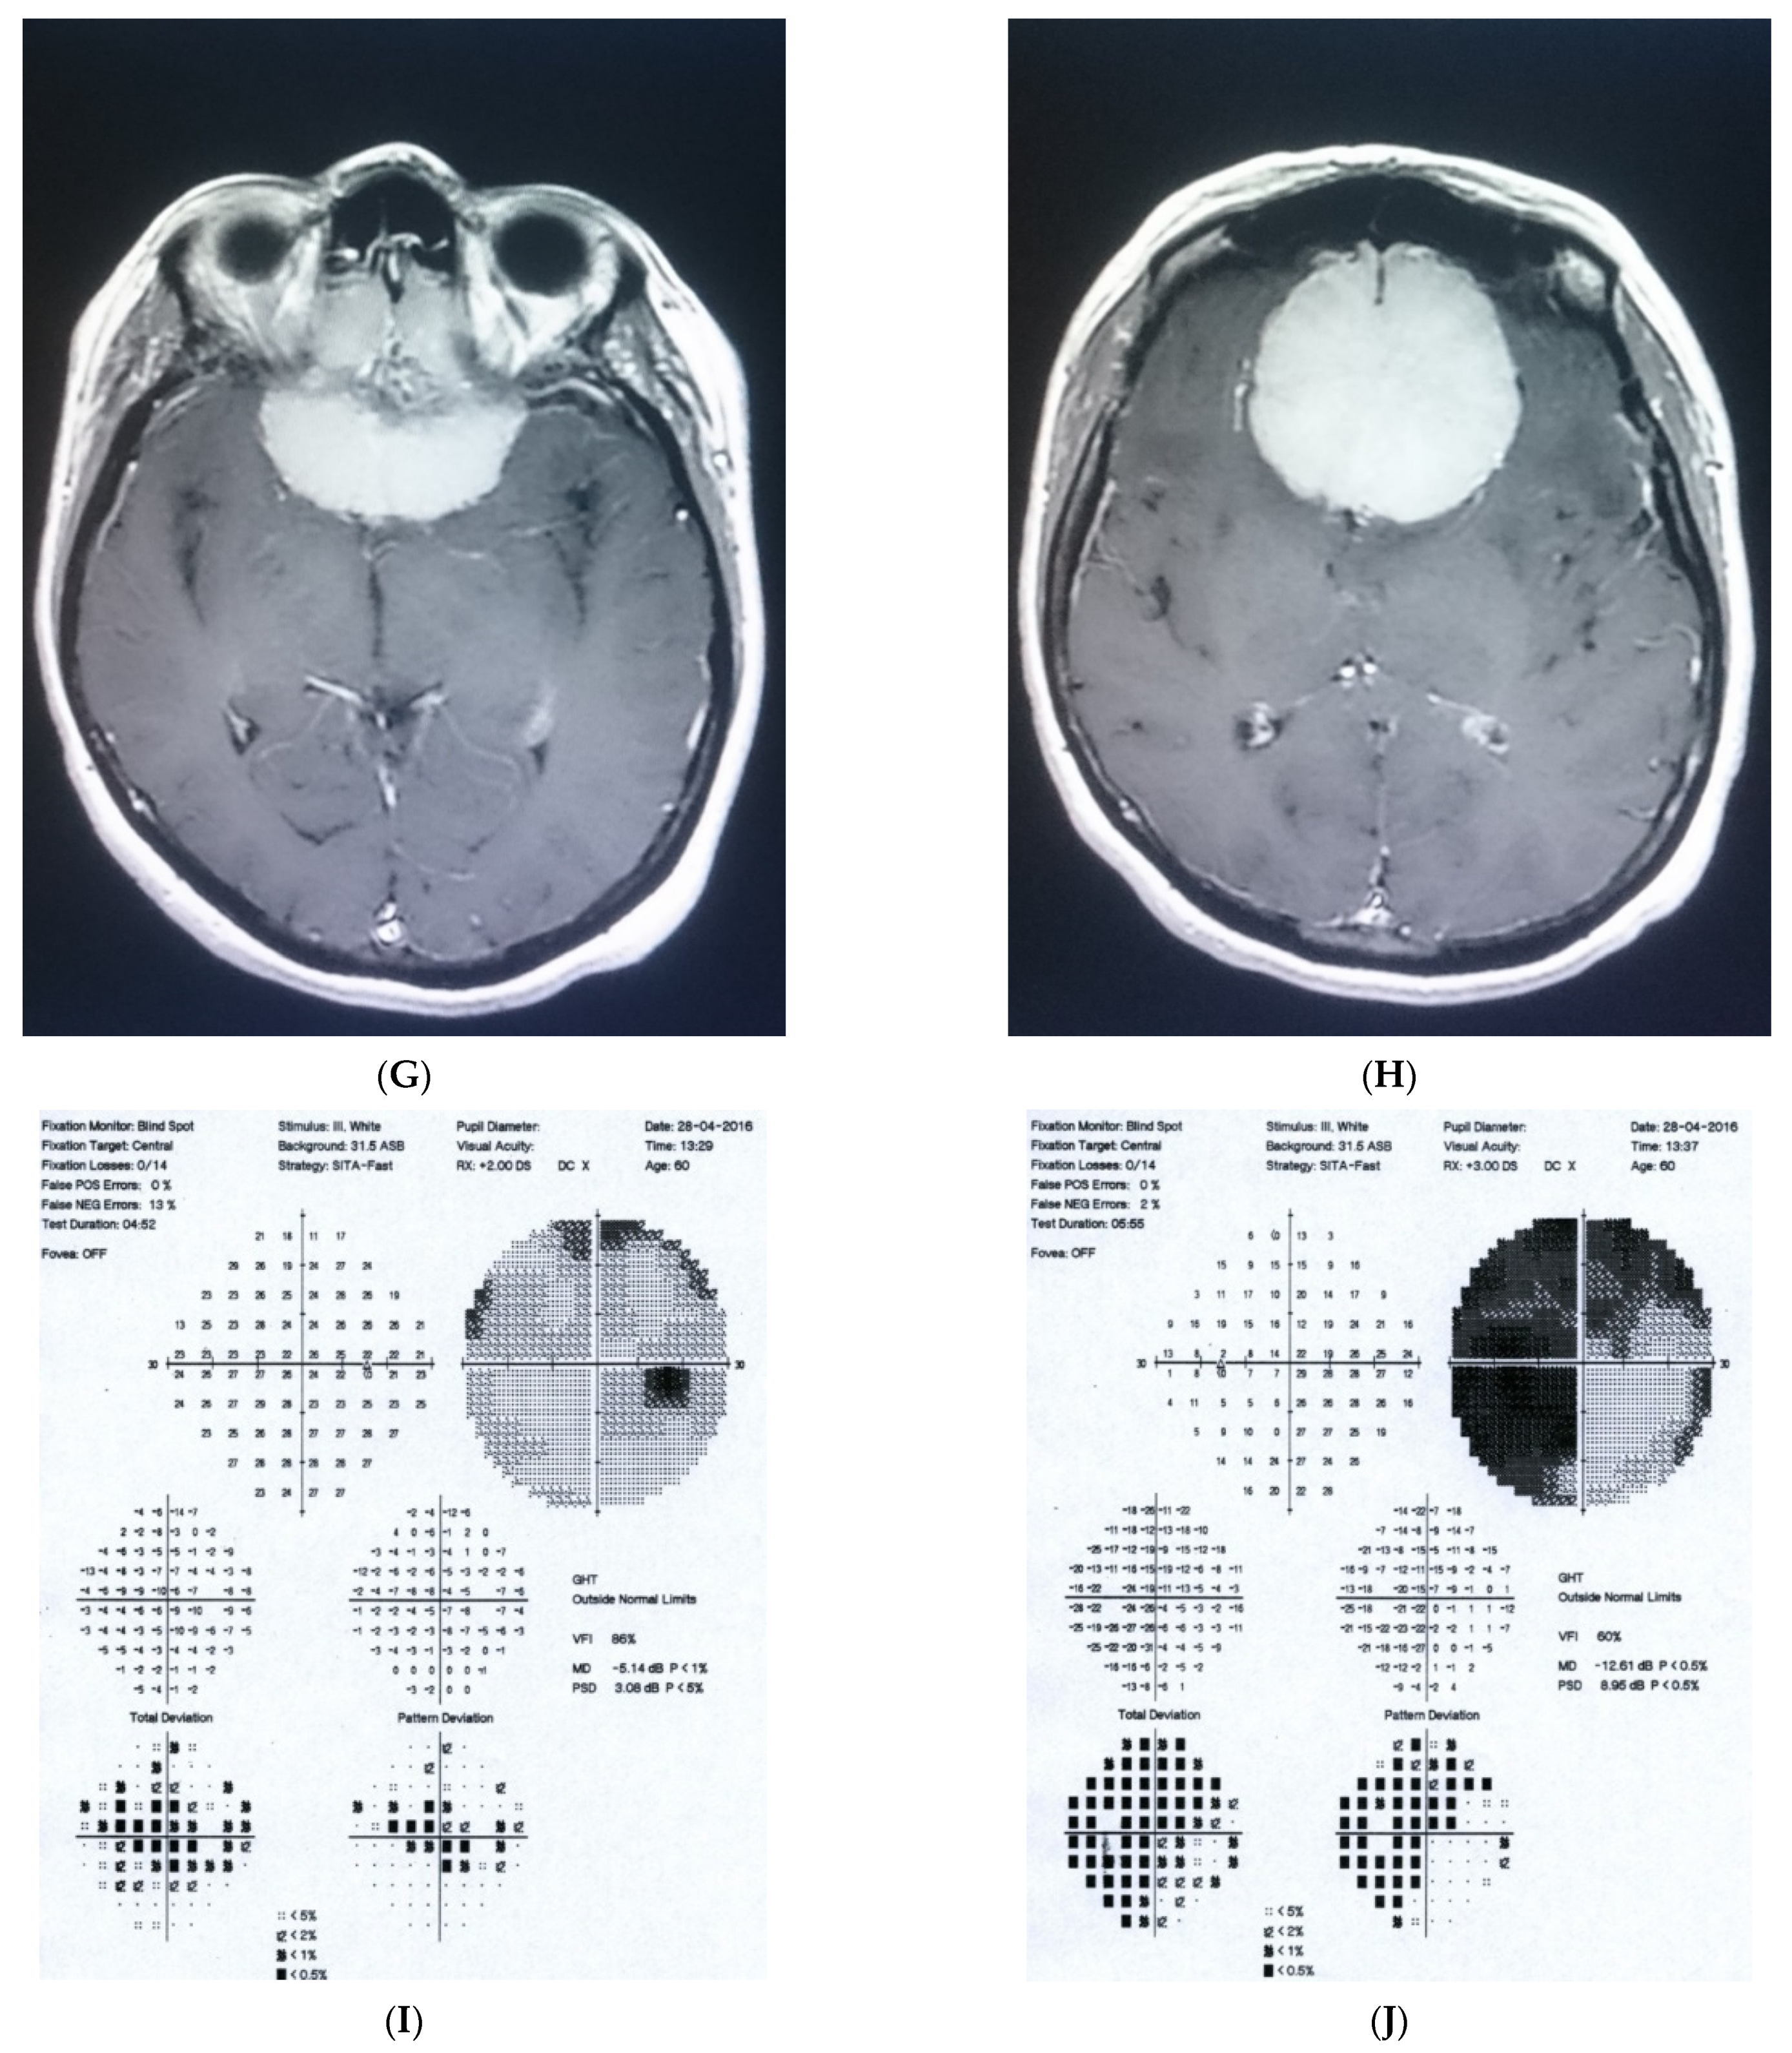

2.4. Case 4

2.5. Case 5